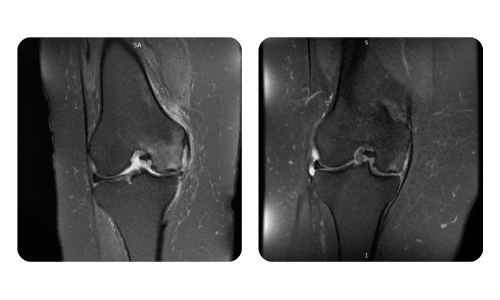

I progressi dei nostri pazienti, misurati prima e dopo la terapia iperbarica, riflettono l'efficacia e l'impatto positivo del trattamento. Scopri i risultati documentati della terapia iperbarica presso la clinica Hyperbarium Oradea, basati su valutazioni cliniche e dati oggettivi che evidenziano miglioramenti significativi in diverse condizioni.